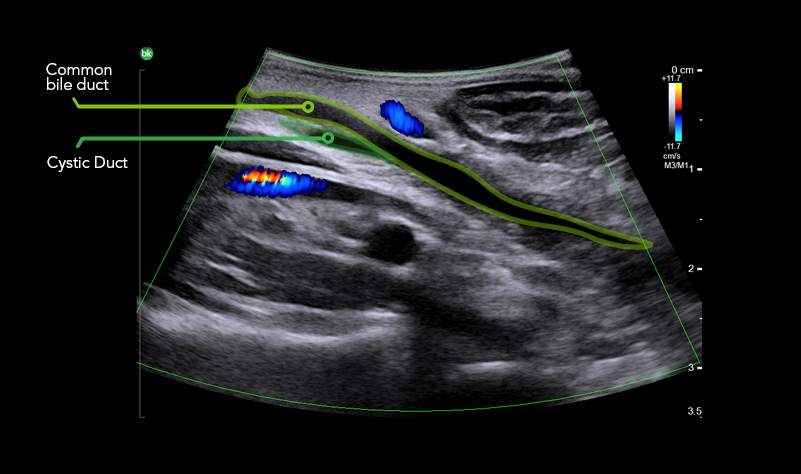

BILIARY TRACT VISUALIZATION

iUS uses color flow doppler to help differentiate between vessels and ducts and is overall effective at imaging difficult cases such as inflammation or fibrosis .1.4 - 6

iUS is highly effective in visualizing biliary anatomy, which can be abnormal in as high as 40% of patient cases.8